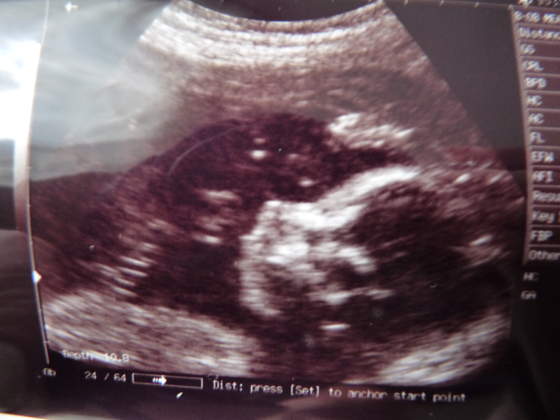

Pati - dzidzia śliczna,